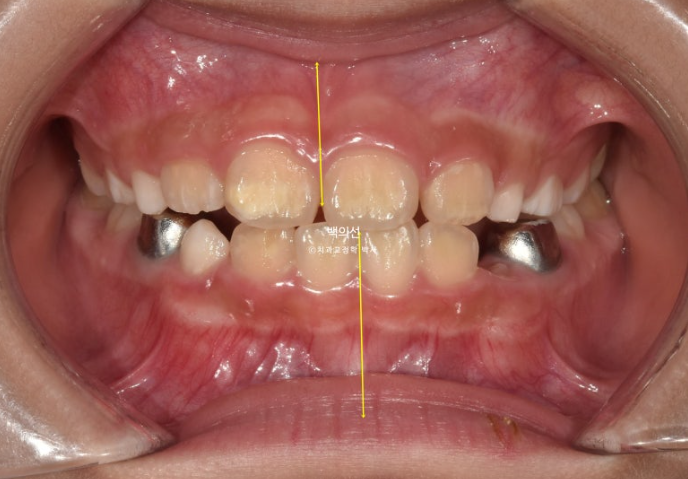

25.03

턱의 위치는 6개월간 자연스럽게 잘 유지가 되었고 치료를 마무리 합니다.

중심선도 아주 잘 맞습니다.

교합은 좋고 이제 막 첫번째 작은어금니가 맹출중입니다.